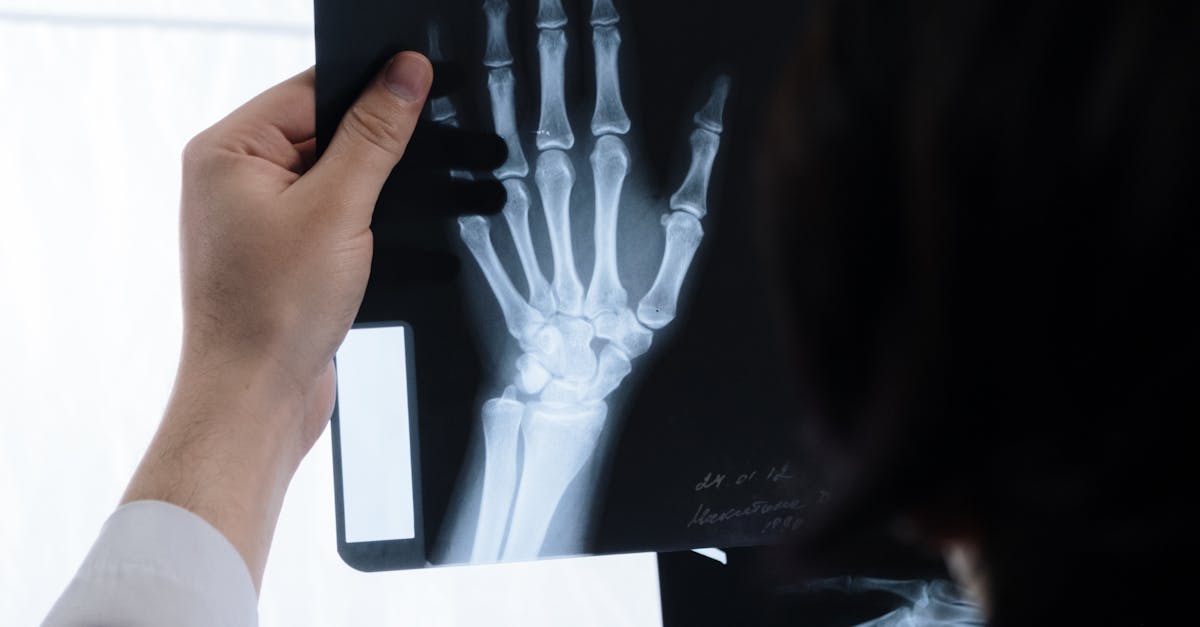

1. Synovial Joint Swelling and Effusion

Photo Credit: Pexels @Funkcinės Terapijos Centras

One of the most prominent and clinically significant appearance changes associated with systemic inflammation is the development of synovial joint swelling and effusion in the wrists and ankles. This phenomenon occurs when inflammatory mediators trigger increased vascular permeability within the synovial membrane, leading to fluid accumulation in the joint space and surrounding tissues. The inflammatory cascade begins with the release of cytokines such as interleukin-1 and tumor necrosis factor-alpha, which stimulate the synovial lining cells to produce excess synovial fluid while simultaneously compromising the normal drainage mechanisms. Visually, this manifests as a characteristic puffiness around the affected joints, with the normal anatomical contours becoming obscured by the accumulated fluid. In the wrist, this swelling typically appears as a loss of the normal depression between the tendons on the dorsal surface, while in the ankle, it presents as fullness around the malleoli and loss of the normal hollows anterior and posterior to these bony landmarks. The degree of swelling often correlates with the severity of the underlying inflammatory process, making it a valuable clinical indicator. Additionally, the affected joints may feel warm to the touch due to increased blood flow, and the skin may appear taut and shiny as it stretches to accommodate the increased volume beneath.